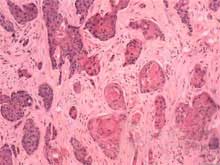

2.病理學檢查 可見角膜上皮異常增殖,層次變厚,鱗狀細胞呈乳頭狀增生基底細胞變大,且有明顯的大小不一,排列不整可出現角化或不全形化,細胞極性紊亂,有異形性,可見核分裂象,其特徵是癌細胞突破上皮基底膜侵犯角膜實質層。

確診依靠病理學檢查。